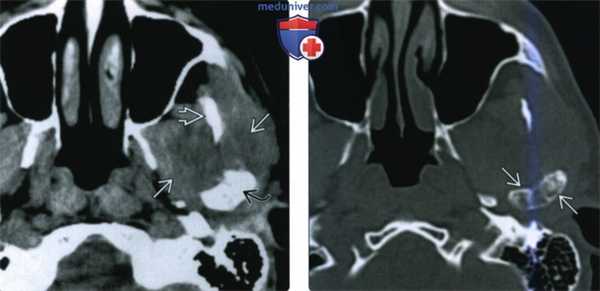

(Слева) На аксиальной КТ без КУ определяется ХС правого мыщелка, снаружи от которого видны множественные плотные включения в отсутствие явного объемного образования. Внутренний край мыщелка склерозирован. Обратите внимание, насколько правый мыщелок отличается от неизмененного левого.

(Справа) На корональной реформатированной КТ без КУ у этого же пациента в мягких тканях визуализируется кольцевидный кальцинат с гиподенсным центром. Определяется деструкция стенок суаавной ямки и большого крыла клиновидной кости. Мыщелок увеличен.

(Слева) На сагиттальной МРТ (Т1 ВИ) у этого же пациента вокруг мыщелка визуализируется многокамерное объемное образование, вовлекающее суставную ямку и большое крыло клиновидной коои.

(Справа) На аксиальной MPT (Т1 ВИ С+ FS) у этого же пациента определяется обширное контрааное усиление солидного объемного образования, окружающего мыщелок, что позволяет исключить его воспалительный характер.